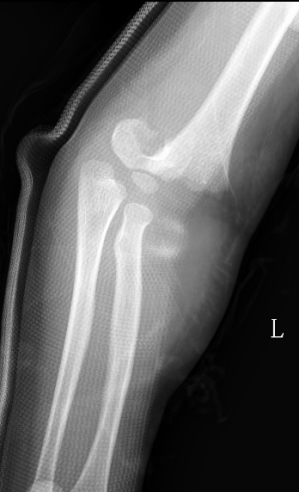

1、小红(化名):女、6岁、吊单杠时不慎摔伤致左肘部肿痛、畸形、活动受限2小时就诊我院。(下图为患儿术前X线片及CT检查)

此种类型的骨折称为肱骨髁上骨折,在完善相关辅助检查后予行麻醉下平乐郭氏手法正骨经皮钢针内固定治疗,术后患儿恢复良好,手术部位只有几个小针眼。(下图为患儿术后X线片)